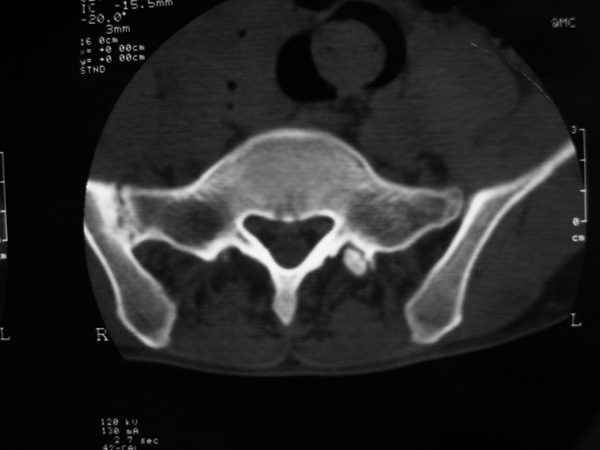

以下是引用w_jianhua在2007-3-8 11:14:00的发言:[br]椎小关节及右侧骶髂关节关节面毛糙,间隙不规则狭窄,骨皮质增生硬化,支持强直性脊柱炎,并椎间盘膨出

以下是引用fumaogui在2007-3-8 8:40:00的发言:[br]腰椎椎间关节增生硬化,关节间隙变窄,右侧骶髂关节间隙变窄,关节面硬化[br]考虑强直性脊柱炎.建议结合化验查:c--反应蛋白和类风湿因子.